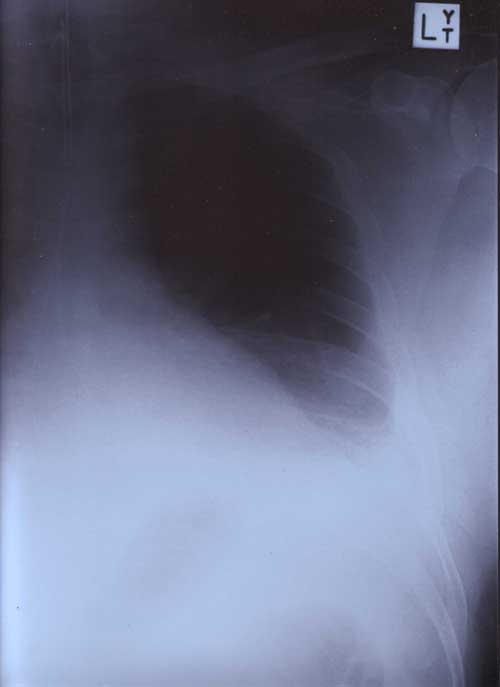

22nd January 2000